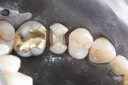

Joe Cha #29 finish